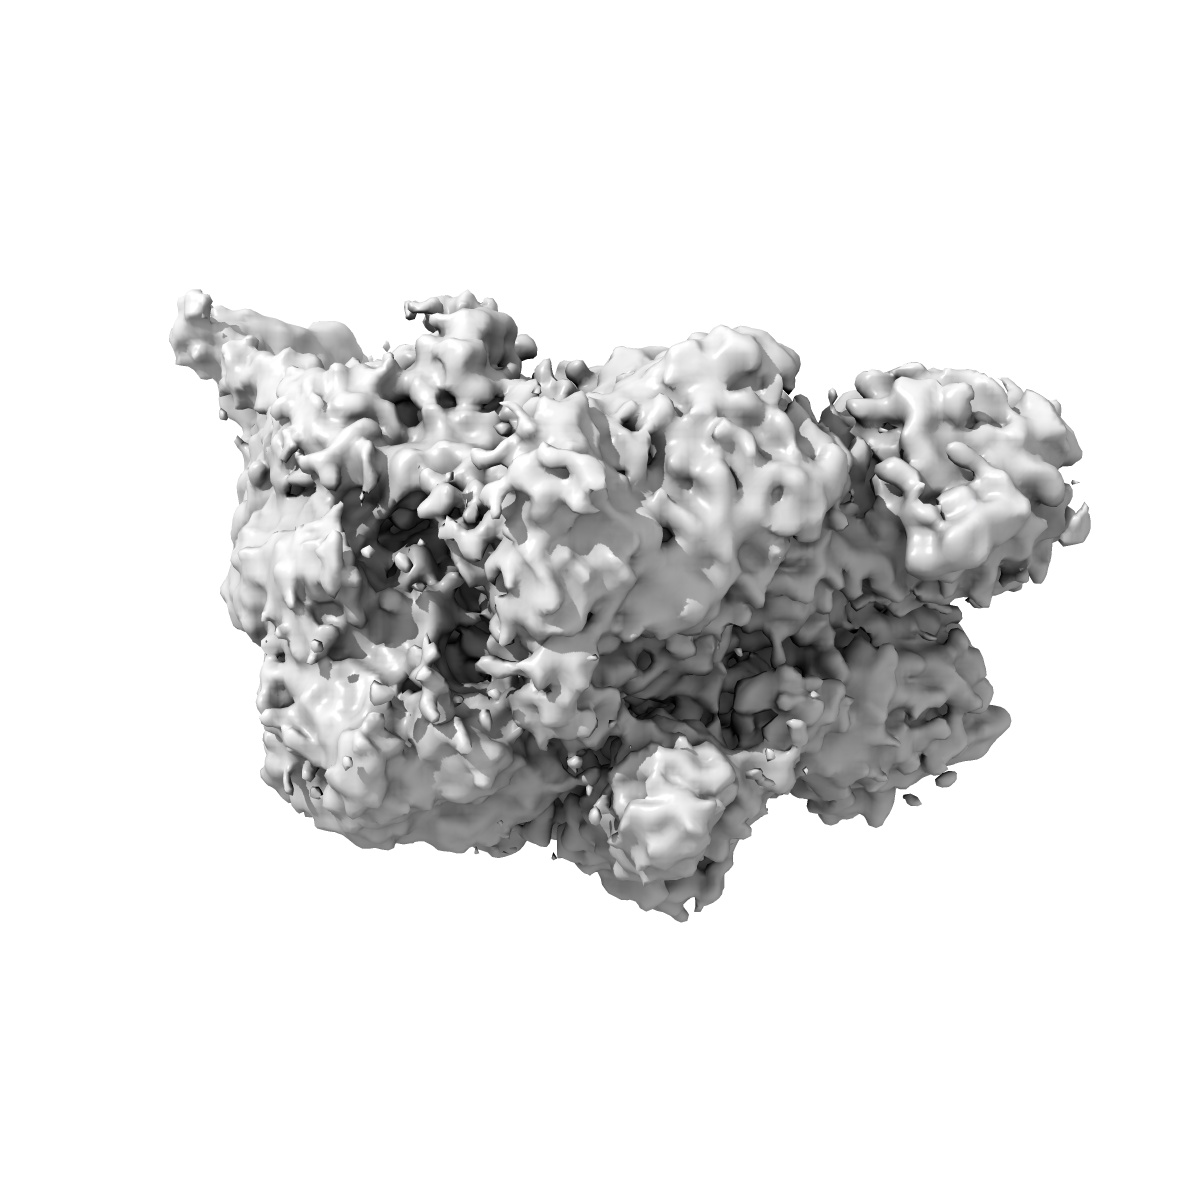

Cryo-EM structure of factor Va bound to activated protein C

Cryo-EM structure of coagulation factor Va bound to activated protein C.